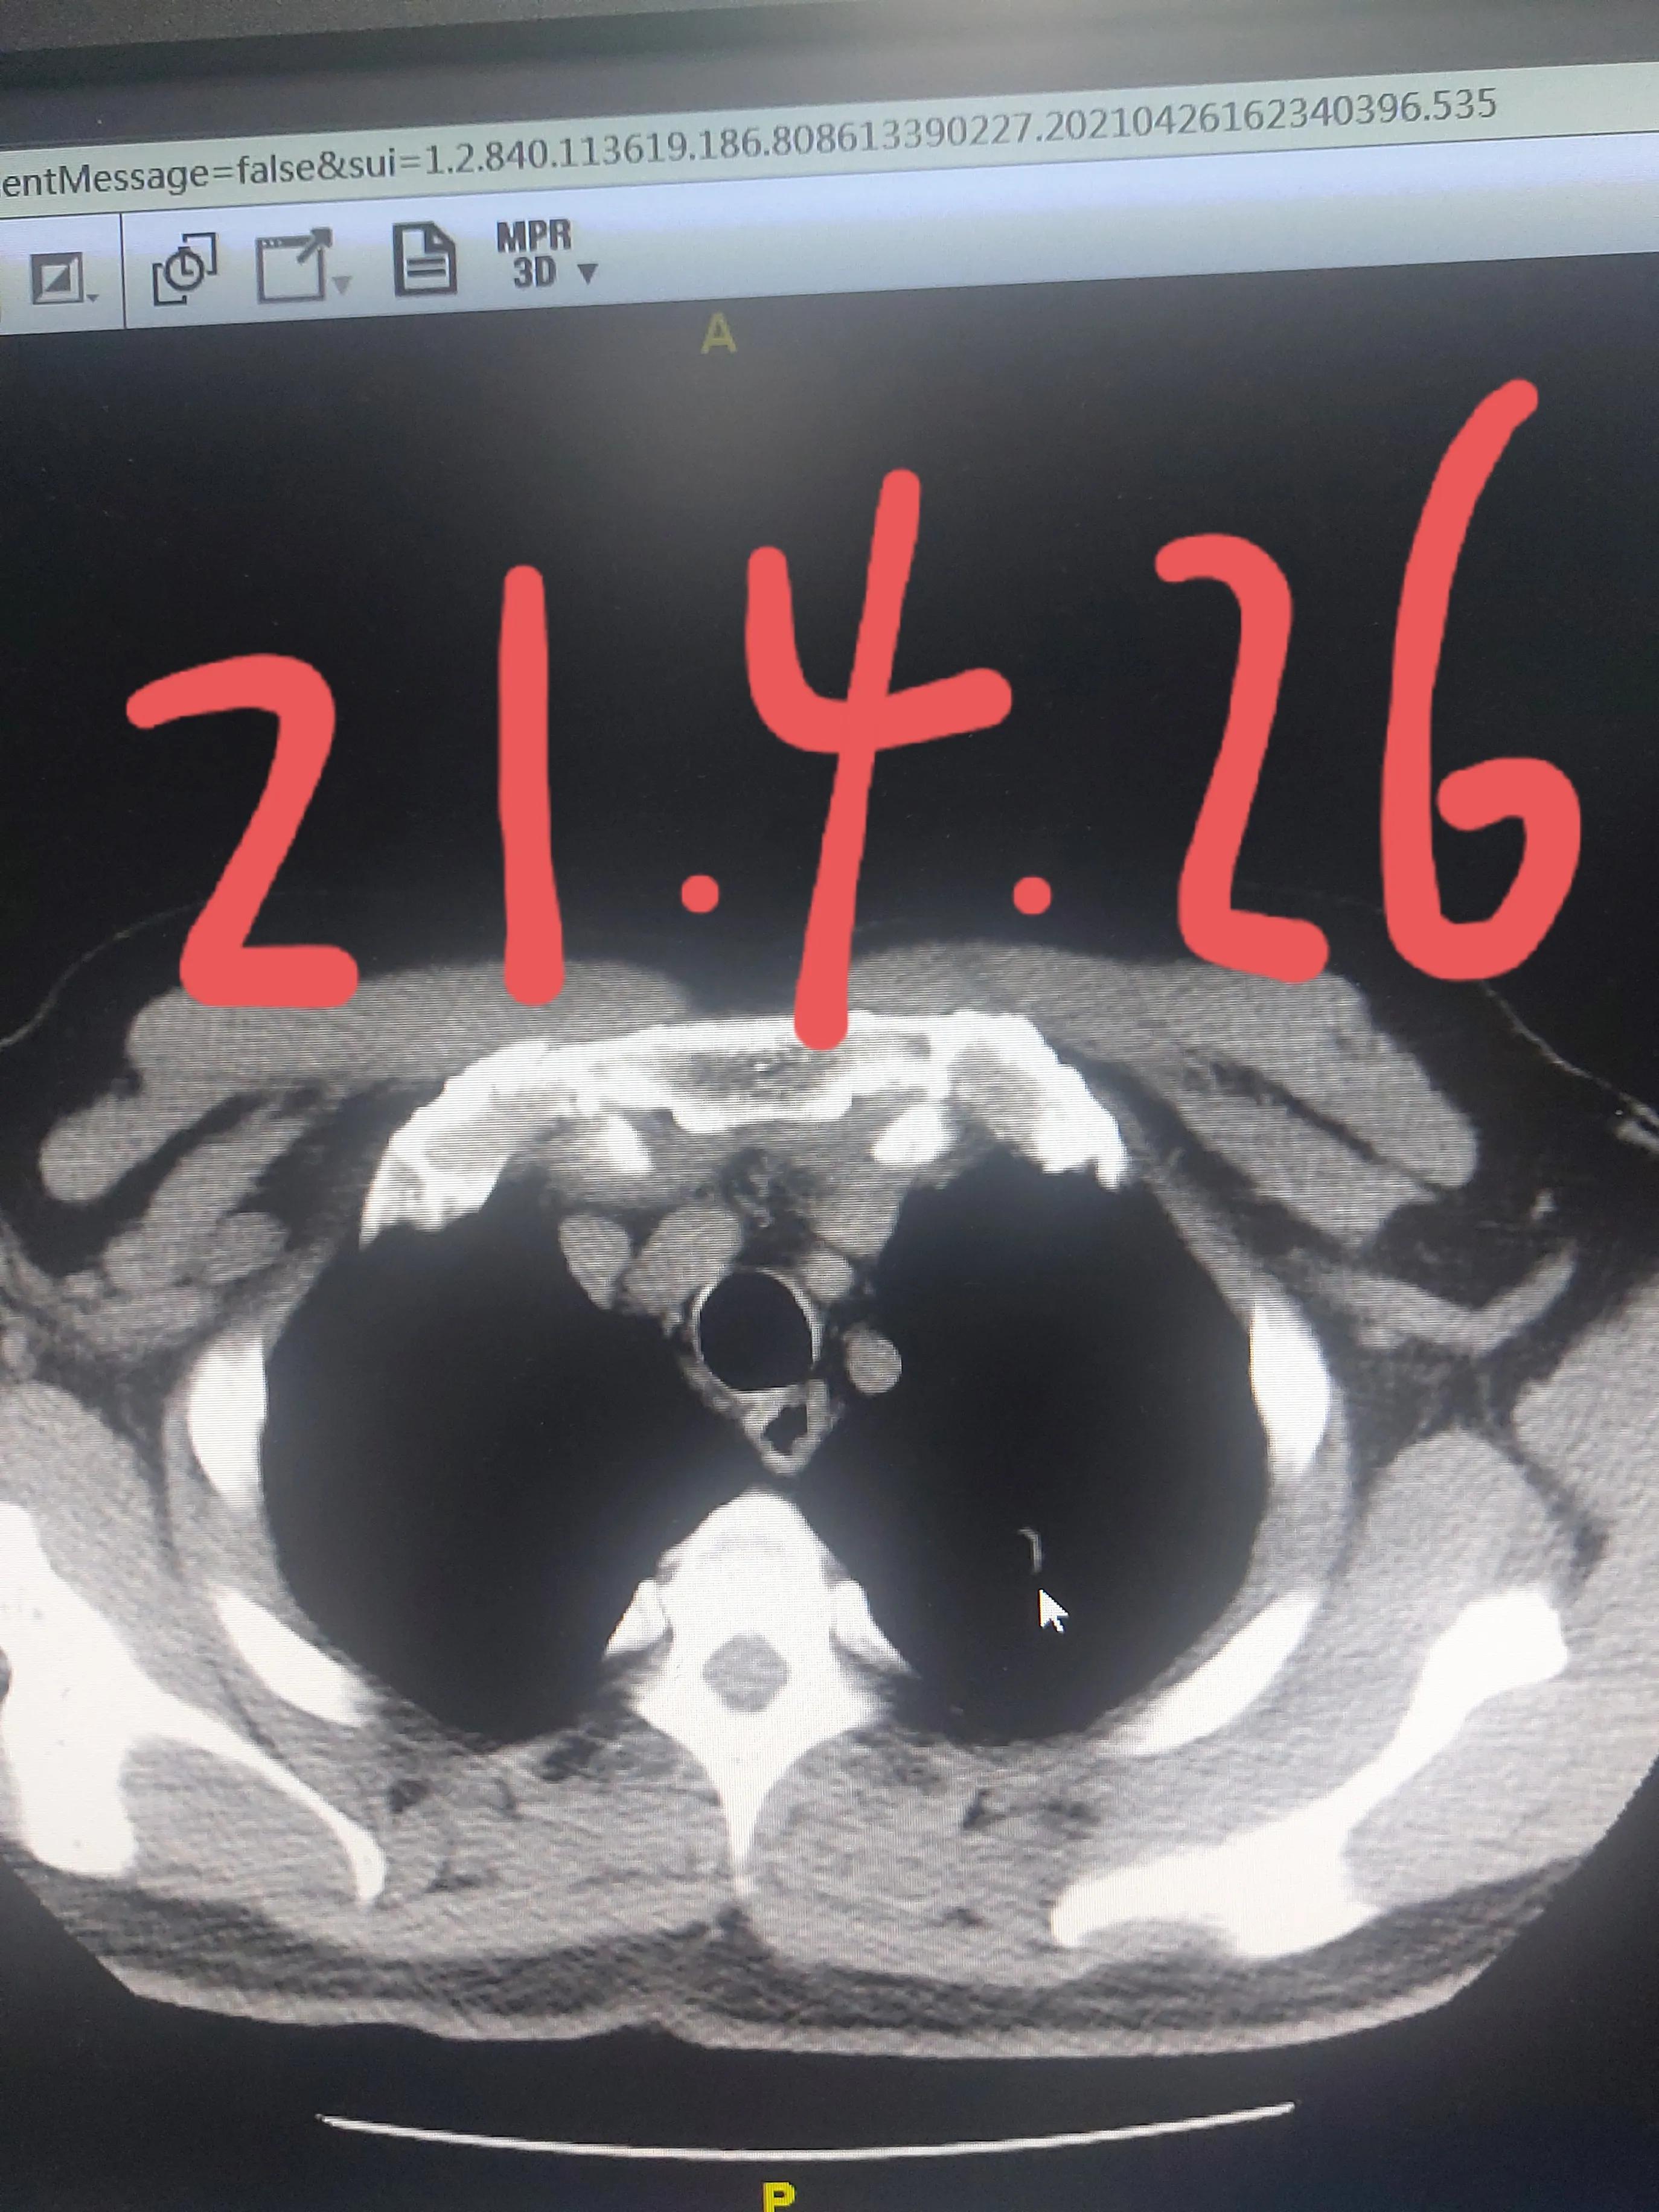

家属听从了我的安排,我给安排好了抗炎治疗,经过了一个疗程的治疗,距离上次一个月复查了胸部CT,果然这个结节比之前变小,并且出现了空洞,种种迹象表明这是一个良性的结节,我告诉他现在更不需要紧张了,目前不考虑是肺癌,定期再来复查就可以了,肯定不需要手术。

通过这个病例,我们知道,如果是炎性的肺结节,是可以通过抗炎之后变小的,如果是癌性的肺结节,那有可能不变或者变小的不明显,如果您发现了肺部结节,一定请专业的肺外科医生来阅片,听听他们的意见,不要盲目的动刀或者给自己陷入恐慌之中不能自拔。有朋友可能很奇怪,你一个外科医生,天天写患教短文,告诉别人不要轻易做手术,别的外科医生都是建议病人抓紧做手术,你不想赚钱吗?虽然我从事这个行业已经20多年了,年龄也不小,但始终保持对医学有一颗敬畏的心,什么样的病人需要手术,什么样的病人不需要手术,一定要以客观的病情为准,而不是以掺杂其他的经济利益为准,对待每一个病人,都要全力以赴,对得起自己的内心。